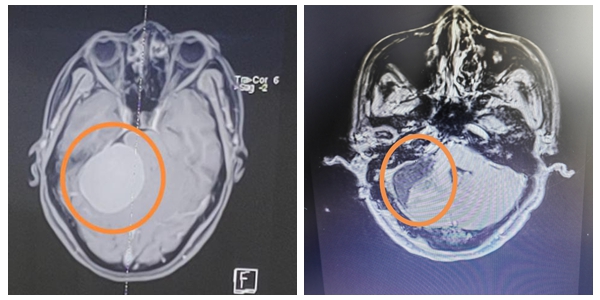

近日,湘雅常德医院神经外科团队再次为一名患者成功实施一例经典颅底大手术:巨大右侧桥小脑角肿瘤切除术+脑脊液漏修补术。手术效果良好,患者听力及吞咽功能保留,目前该患者已顺利康...

近日,湘雅常德医院神经外科在袁贤瑞教授和张梨副主任医师的带领下成功开展了一例桥小脑角区巨大脑膜瘤切除术。 近年来,朱阿姨的耳边持续性出现“嗡……嗡……...